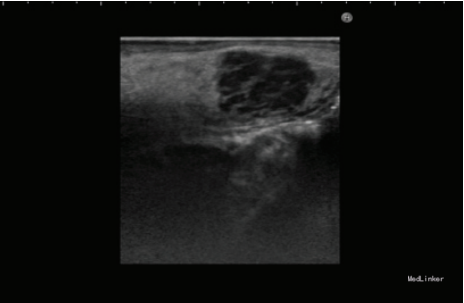

检查发现舌下有一隆起,约1.2*1cm大小,未影响舌功能和运动,唾液分泌正常,周围淋巴结无肿大。 影像检查显示右舌有一不规则圆形肿物,边界不清。